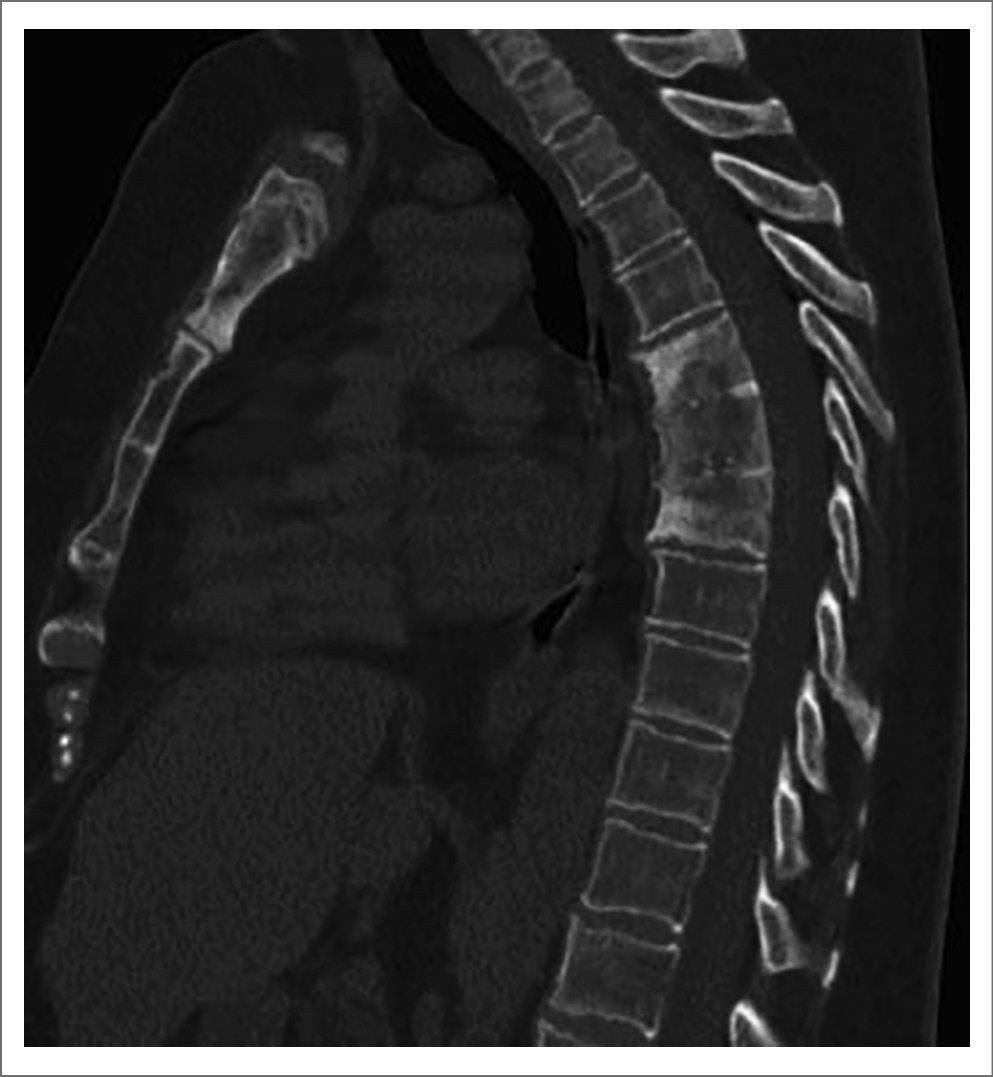

Могут быть найдены и рентгенологические изменения позвоночника в виде остесклероза замыкательных пластинок, развития энтезофитов или синдесмофитов, клиновидных деформаций тел и (редко) анкилозирования тел позвонков (рис. 8). Эти изменения обычно ограничены одним сегментом, но иногда распространяются на несколько соседних позвонков. Они напоминают изменения, свойственные анкилозирующему спондилиту, но не бывают столь распространенными [2, 8]. Сакроилиит разных рентгенологических стадий диагностируется у 13–52% пациентов с синдромом SAPHO. На МРТ можно обнаружить признаки переднего и заднего спондилита, артрита дугоотростчатых суставов и активного сакроилиита [2, 10, 24].

Рис. 8. КТ грудной клетки (сагиттальная плоскость) пациентки П., 54 года, с ОАПГК (синдром SAPHO). Определяются изменения грудного отдела позвоночника: клиновидная деформация и сращение тел ThVI, ThVII и ThVIII, эрозирование верхней замыкательной пластинки ThVI и нижней замыкательной пластинки ThVIII, неровность передней поверхности тел, многочисленные участки просветления костной ткани в телах ThVI, ThVII и ThVIII, обширные зоны остеосклероза в телах ThVI и ThVIII, краевые передние остеофиты. Также заметна деформация рукоятки грудины с расширением (гиперостоз) и фрагментацией верхней ее части и зонами просветления и склероза в нижней части (собственное наблюдение [1]).